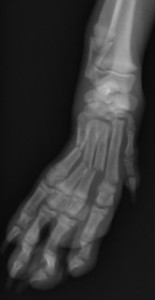

整復前 整復後

高所からの転落により左肩関節を脱臼。鎮静下にて整復→外固定を約2週間実施。